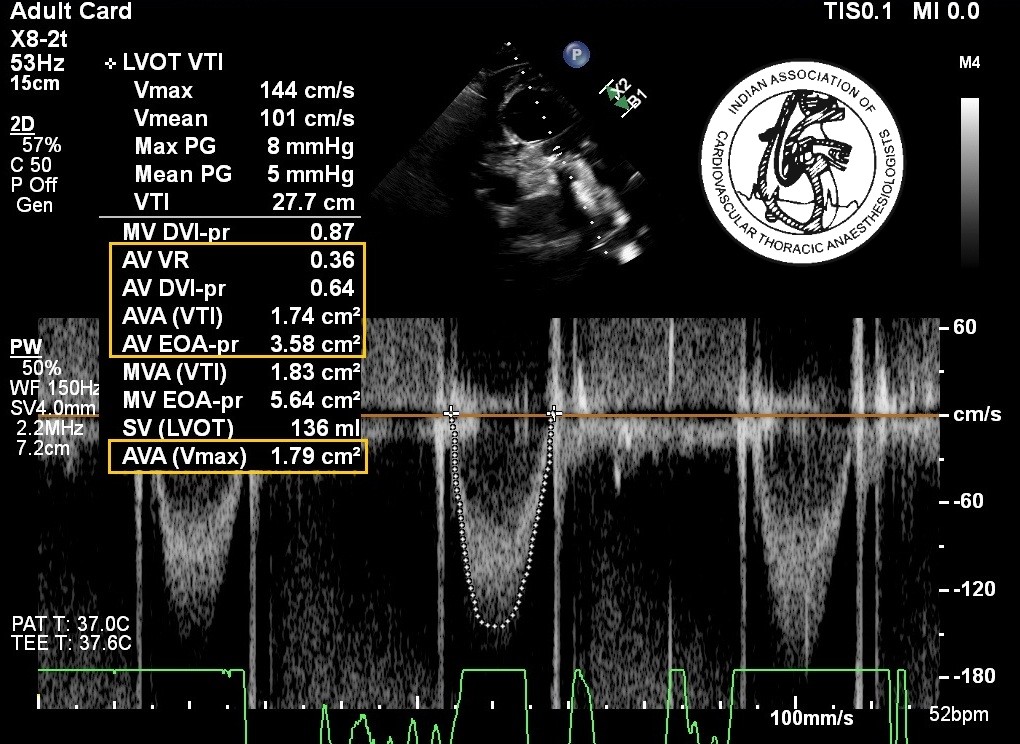

A 60-years-old asymptomatic patient (body surface area 1.5 m2) is diagnosed with severe aortic stenosis. During intraoperative transesophageal echocardiographic examination, the following data are obtained: LVOT peak velocity = 0.6m/s; LVOT velocity time integral (VTI) = 14 cm; LVOT diameter = 1.9 cm; peak velocity across aortic valve = 3m /s; aortic valve VTI = 74 cm, LV ejection fraction of 45%. The patient has a heart rate of 55/min during the study. All of the following statements are correct except:

1.Peak gradient across the aortic valve

Using the modified Bernoulli equation:

P= 4V2= 4(3)2  = 36mmHg

Peak gradient across aortic valve = 36mmHg

Mean Aortic gradient = 0.64 x peak gradient = 23 mmHg (2)

2.Stroke volume

LVOT cross sectional area == pr2 = 3.14 X (1.9/2)2 = 2.84 cm2

Stroke volume = LVOT VTI X LVOT cross sectional area

= 14 X 2.84 = 40 ml

Stroke volume index = stroke volume/ BSA = 40 ml/ 1.5 =26.7ml/m2

Cardiac output = Stroke volume x heart rate = 40x 55= 2200 ml/ min= 2.2L/ min

3.Aortic valve area (Continuity equation)

Aortic valve area= LVOT cross sectional area x LVOT VTI / aortic valve VTI

= 2.84 X 14 / 74

=0.54 cm2

4.Final summary:   Mean gradient = 23 mmHg

Stroke volume index = 26.7 ml/m2

Cardiac output = 2.2 L/ min

Aortic valve area= 0.54 cm2

It is consistent with Low-flow, low-gradient severe aortic stenosis,  as the ejection fraction is 45%.

Correct Answer: d)It is a classic example of moderate aortic stenosis.